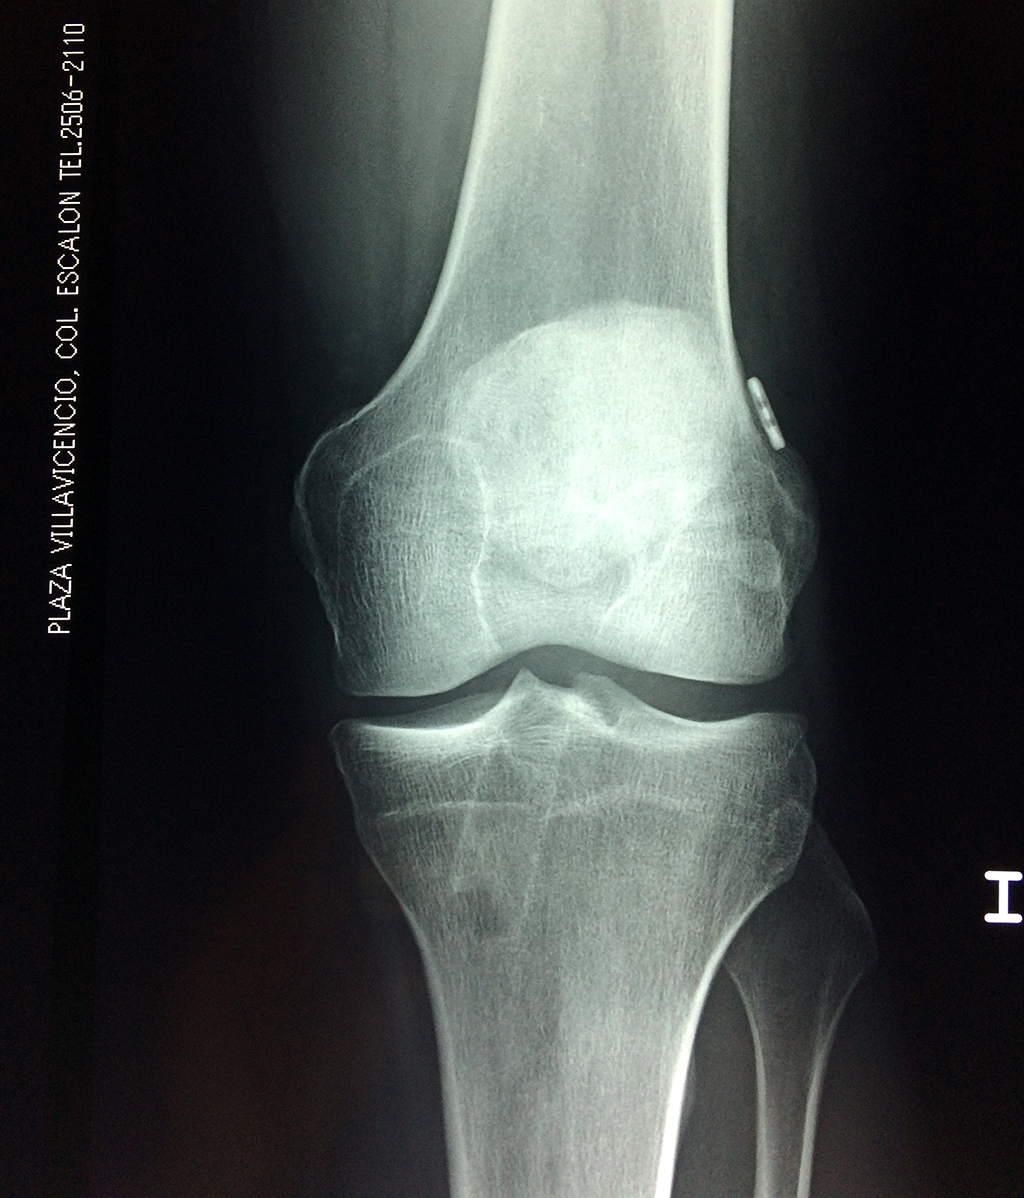

La artroscopia de rodilla es un cirugía en el cual la estructura interna de la articulación es examinada ya sea para realizar un diagnostico o para realizar un tratamiento, este procedimiento se realiza utilizando un instrumento parecido a un pequeño tubo llamado artroscopio.

La artroscopia se popularizo en 1960 y hoy en día es muy común en todo el mundo. Típicamente, es realizada por cirujanos ortopédicos de manera ambulatoria. Cuando se realiza de manera ambulatoria los pacientes pueden regresar a casa después de la operación, no se requiere quedarse en hospital.